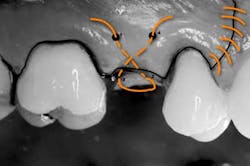

1. A full-thickness flap is reflected to gain access to the lateral wall of the maxillary sinus (Fig. 1). In this area the bone is normally very thin, usually less than 1 mm.Fig. 34. The sinus membrane is separated from the bony wall. Perforations of the membrane occur frequently during this phase. To increase safety and reduce complications, the air-driven sonic handpiece is used, coupled with the discoid insert. The insert is activated (vibrating and irrigated by the water spray) and then placed between the lateral bone wall and the Schneiderian membrane (Fig. 4).